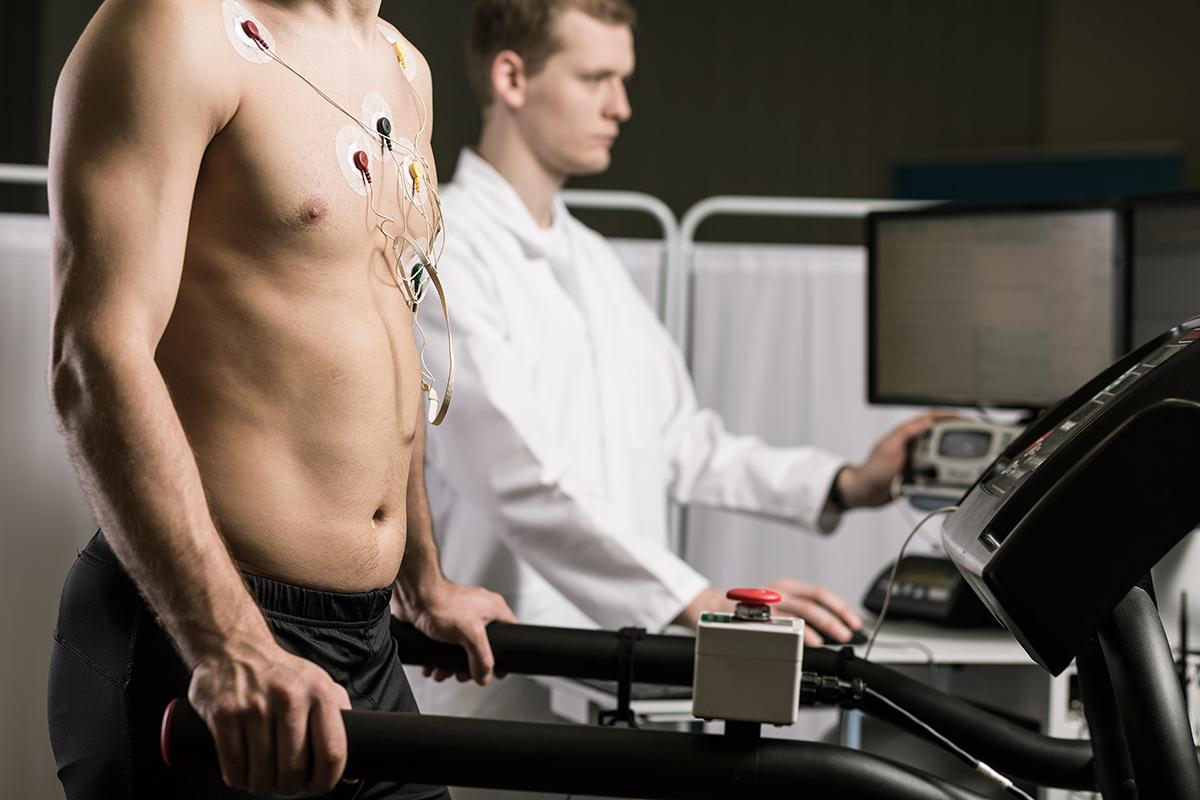

An Evaluation Procedure occurs to involve exercises like walking on a treadmill or cycling in Electrocardiography to monitor the health of your heart.